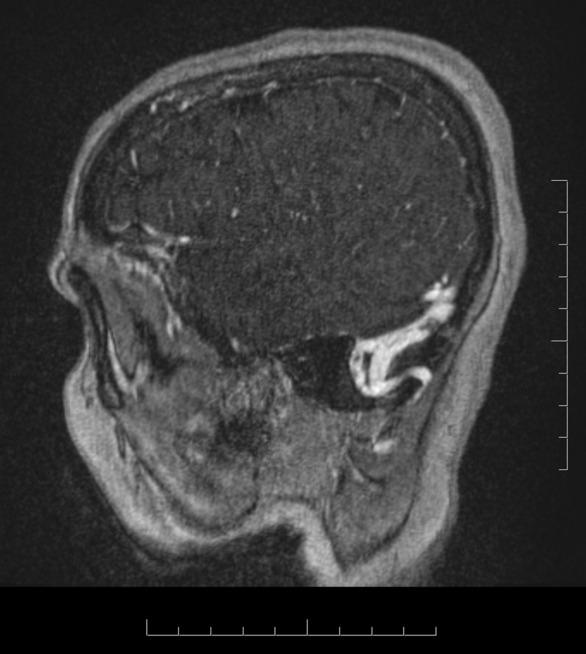

Supine headache and papilledema: A case and review of cerebral venous sinus thrombosis.

Cerebral venous sinus thrombosis (CVST) is a rare cause of stroke and is on the differential for intracranial hypertension. Non-contrast head CT is often normal. CT venogram or MR venography are the preferred diagnostic tests, as was required in our patient. We review the presentation, diagnosis, and management of CVST.